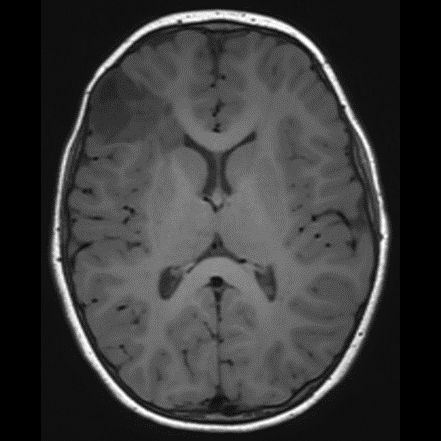

DNET:Özellikle erkek çocuk ve nöbet öyküsüyle gelen hasta kortikal yerleşim ve t1 ağırlıklı serilerde hipointens t2a ve flair serilerde ise hiperintens görülmesi bu tanıma uymaktadır. Hastaların 5’te birinde frontal lobda da tutulum olabilir. Lezyon çevresinde ödem ya da içerisinde kalsifik odak izlenmemiştir:

DNET:Özellikle erkek çocuk ve nöbet öyküsüyle gelen hasta kortikal yerleşim ve t1 ağırlıklı serilerde hipointens t2a ve flair serilerde ise hiperintens görülmesi bu tanıma uymaktadır. Hastaların 5’te birinde frontal lobda da tutulum olabilir. Lezyon çevresinde ödem ya da içerisinde kalsifik odak izlenmemiştir.